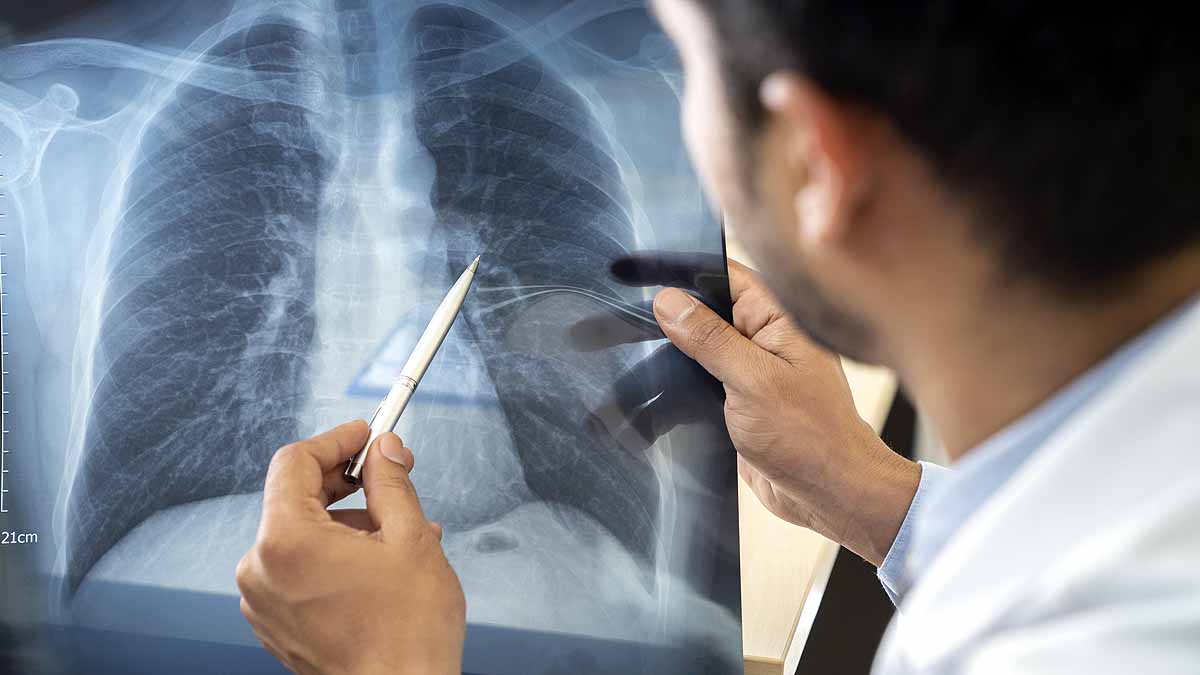

शोधकर्ताओं ने देखा कि RAS कोशिकाएं फेफड़ों पर निर्भर रहने से फ्रस्टेट होने लगती हैं. क्योंकि उनका पूरा काम फेफड़ों से संबंधित प्रणालियों से ही चलता है. लेकिन बदले में उन्हें कुछ नहीं मिलता. असल में इन सभी सवालों के जवाब पाने के लिए वैज्ञानिकों ने एक स्वस्थ इंसान के फेफड़ों का टिश्यू यानी ऊतक लिया. इसके बाद हर कोशिका के अंदर मौजूद जीन्स का विश्लेषण किया, तब RAS कोशिकाओं का पता चला.  (फोटोः गेटी)

यूनिवर्सिटी ऑफ पेंसिलवेनिया के पेरेलमैन स्कूल ऑफ मेडिसिन के प्रोफेसर एडवर्ड मॉरिसे ने कहा कि यह बात तो पहले से पता था कि इंसानी फेफड़ों की शाखाएं यानी हवाओं के आने-जाने का मार्ग चूहों के फेफड़ों से अलग होते हैं. नई तकनीकों के विकसित होने से हमें यह फायदा हुआ कि हम इस नई कोशिका को खोज पाए. हम उसके सैंपल की जांच कर पाए.  (फोटोः गेटी)